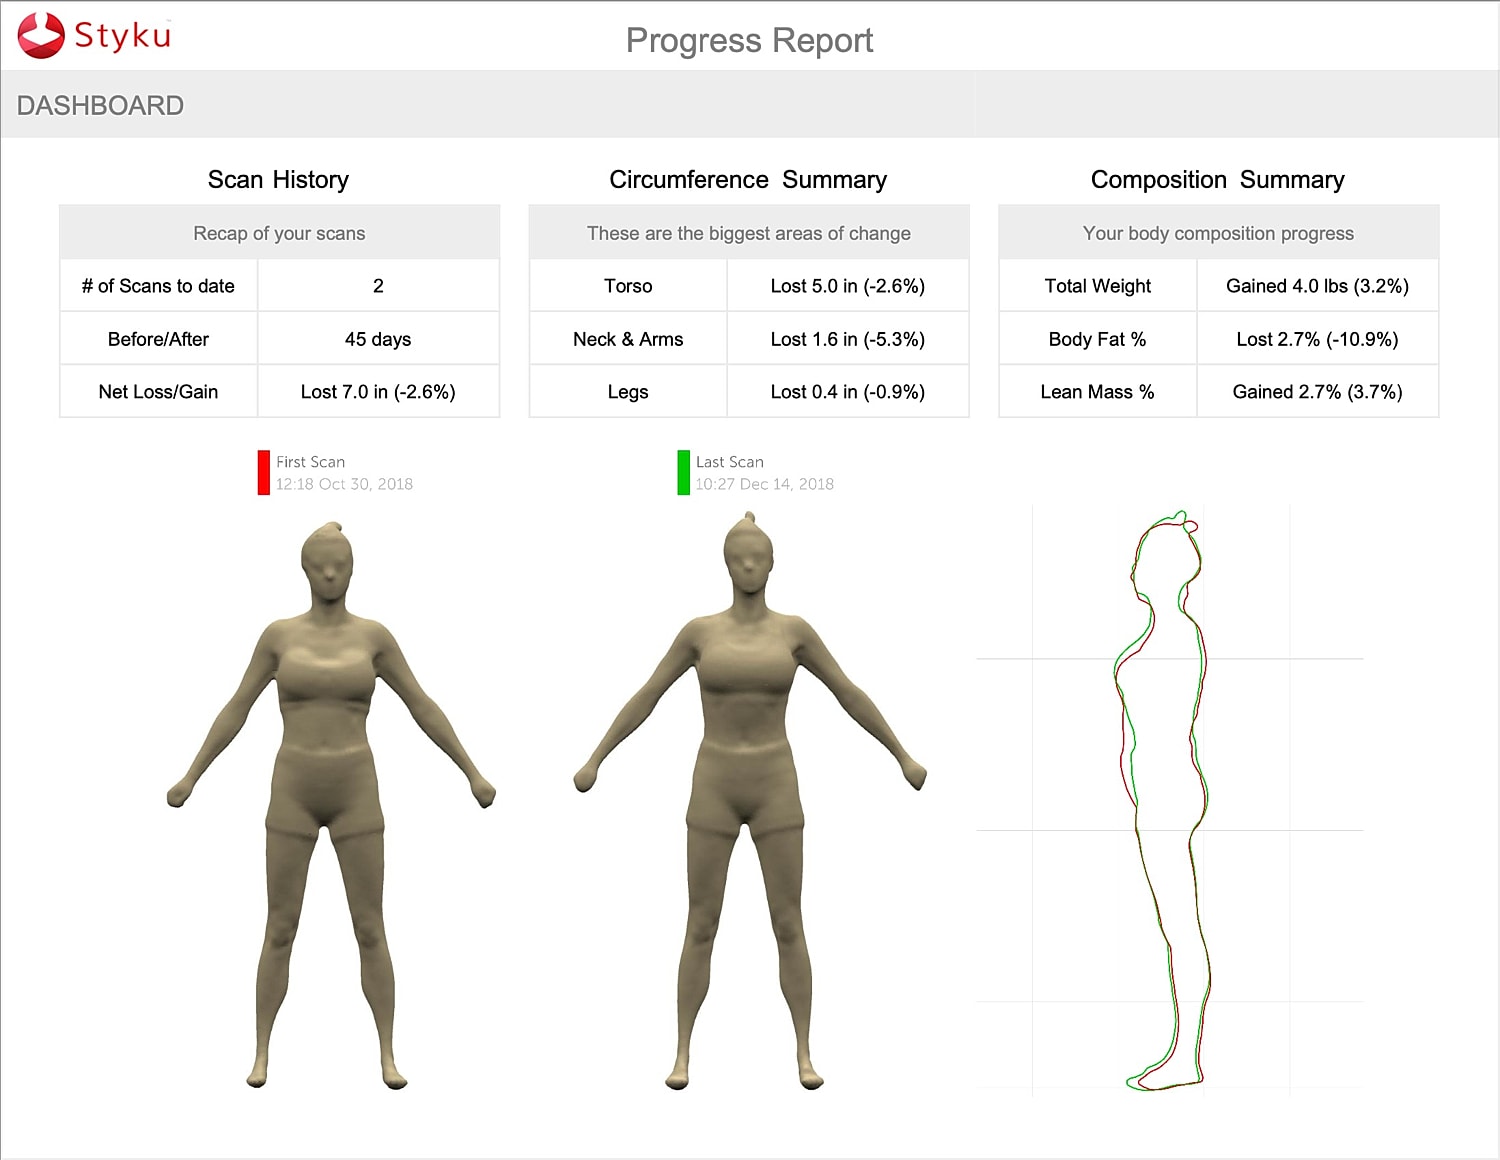

Styku 3D body scanning at sculpMD Performance Clinic delivers a precise, visual snapshot of your body’s composition and posture. Using advanced infrared technology, Styku captures accurate measurements, fat distribution, and progress over time — far beyond what a scale can tell you. This non-invasive scan is quick, radiation-free, and essential for setting personalized fitness, weight management, and health goals with confidence and clarity.

Your journey begins with understanding — not assumptions. We take a science-driven, personalized approach to your health, performance, and body composition, beginning with advanced assessments like metabolic testing with PNOĒ, Styku 3D body scans, and focused lab work.